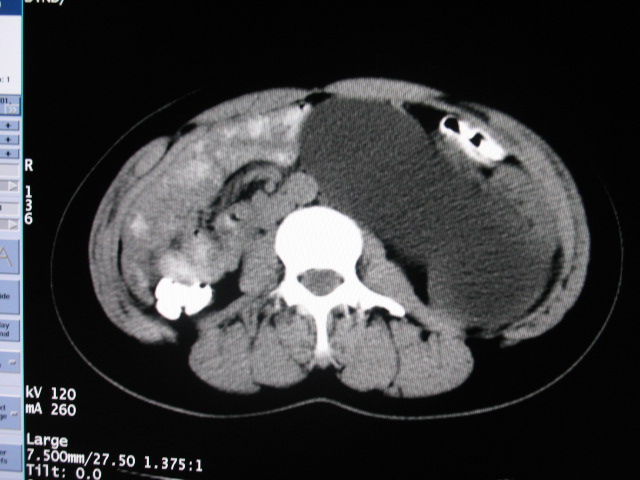

女,28岁,自觉腹部包块一年余

左侧为扩张的输尿管,一直延续到膀胱,那么它的上端应该是扩张的肾盂,但是在他的下方我们看到一个比较正常的肾,所以考虑左侧重复肾盂输尿管畸形。

考虑左侧双肾盂双输尿管畸形,其中一输尿管末端梗阻(不排除异位开口可能)并相应之肾盂及输尿管明显扩张积水。

左侧重复肾、双输尿管畸形。重复肾一般上位肾发育不良,易合并积水。

术后证实是左侧双肾盂双输尿管畸形,巨输尿管巨肾盂症